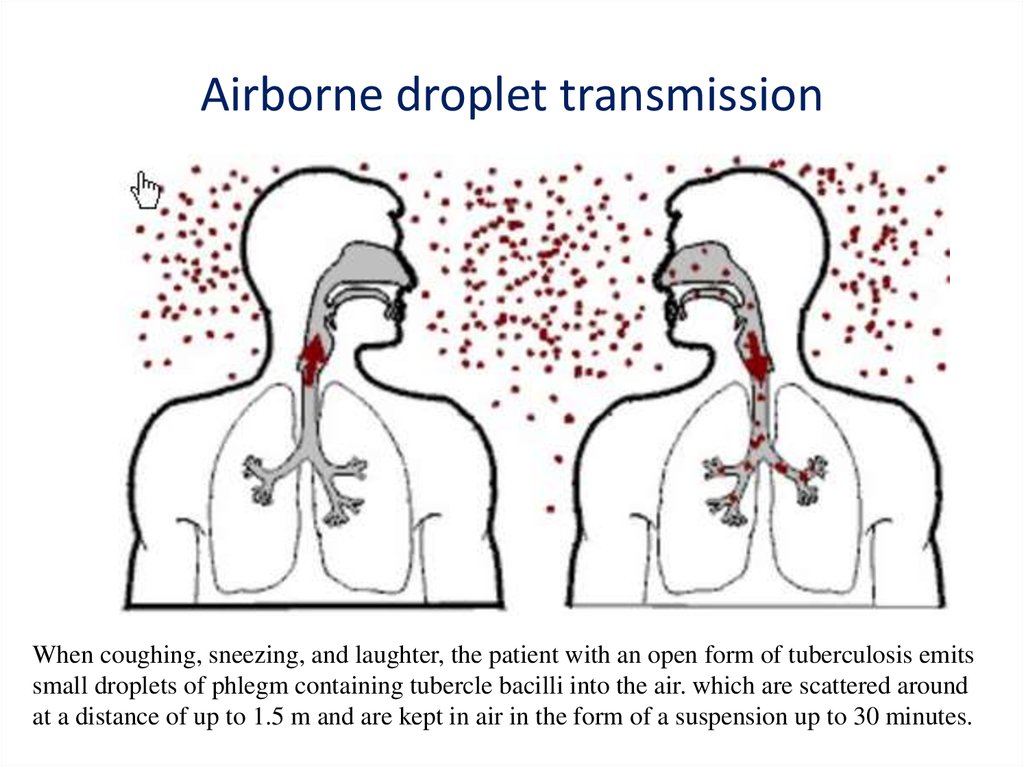

How do you get TB?

You can get TB by breathing in air droplets from a cough or sneeze of an infected person. The resulting lung infection is called primary TB. Most people recover from primary TB infection without further evidence of the disease. The infection may stay inactive (dormant) for years.

Causes. Pulmonary TB is caused by the bacterium Mycobacterium tuberculosis (M tuberculosis). TB is contagious. This means the bacteria are easily spread from an infected person to someone else.Dec 24, 2020

The bacterium Mycobacterium tuberculosis causes tuberculosis (TB), a contagious, airborne infection that destroys body tissue. Pulmonary TB occurs when M. tuberculosis primarily attacks the lungs. However, it can spread from there to other organs. Pulmonary TB is curable with an early diagnosis and antibiotic treatment.